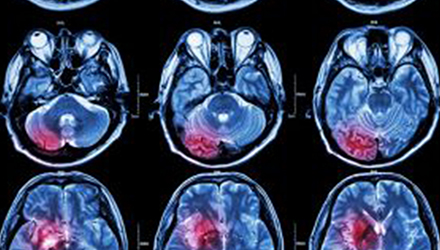

在這項研究中,研究人員使用功能核磁共振成像(fMRI)觀察大腦中血液含氧量的變化。研究人員首先研究了耳鳴患者和無耳鳴者的大腦活動,其目的是比較兩組受試者大腦處理情緒的方式。

在功能磁共振成像檢查中,受試者分別聽30種“愉悅”的聲音、30種“不愉快”的聲音和30種“中性”的聲音。這些聲音包括小孩咯咯笑,嬰兒啼哭,以及熱水壺燒開的聲音。

功能磁共振成像的結果顯示,當暴露于情緒性聲音下,耳鳴患者大腦不同區(qū)域的活動比沒有耳鳴者的活動更強烈。接著,研究人員進行了更深入的研究:耳鳴患者的大腦活躍性和耳鳴嚴重程度的關系。

調查結束后,再進行功能核磁共振成像檢查。第二輪功能核磁共振成像顯示,那些耳鳴較輕的患者實際上使用了大腦不同的區(qū)域來處理情緒信息。

傳統(tǒng)觀點認為,大腦中的扁桃體是處理情緒的關鍵,但此次研究發(fā)現(xiàn),那些不被耳鳴困擾的患者實際上使用更多大腦額葉來處理情緒。這類患者額葉活動更顯著的原因是,額葉通常更多地用于注意力、計劃和沖動的控制。